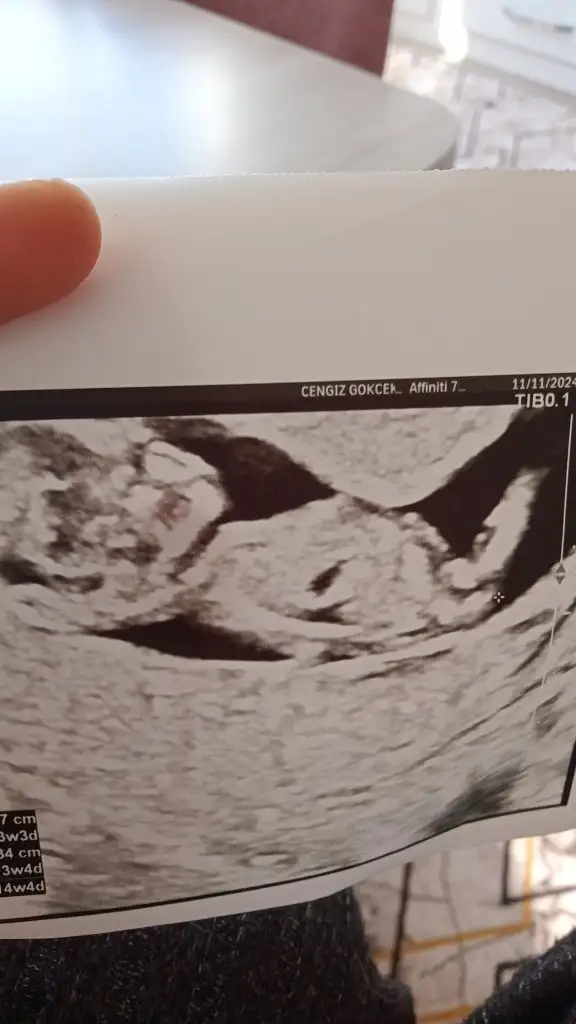

13 hafta cinsiyet nedir sizce yorumlar musunuz lütfenkız gibi

Kız gibi canım13 hafta cinsiyet nedir sizce yorumlar musunuz lütfen

Tabi öyle doktorlar dahi yanılıyor ama merak işteKız gibi canım

Kız gibi erkeğin kesesi genelde fasulyeye benziyoTabi öyle doktorlar dahi yanılıyor ama merak iştebu da 8 hafta görüntü belki yüzdelik verebilirsiniz